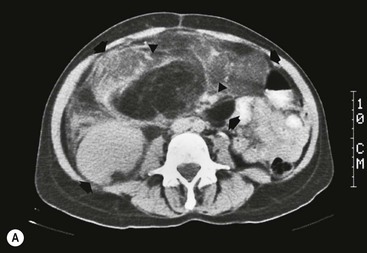

Lymphangioma represents a congenital malformation of the lymphatic vessels arising from the bowel. The typical imaging appearance is that of a large, thin-walled, single or multiloculated cystic mass, with contents of water-to-fat attenuation on CT (Fig. 30-4) and of high signal intensity on T2-weighted MR images. Enhancement of the cyst wall and septa is seen. It is frequently closely associated with the small bowel. US is helpful in demonstrating the internal septations of the cystic mass.8

Large mesenteric lymphangiomas can be differentiated from ascites by the presence of septa, compression on adjacent intestinal loops and lack of fluid in the dependent peritoneal recesses.